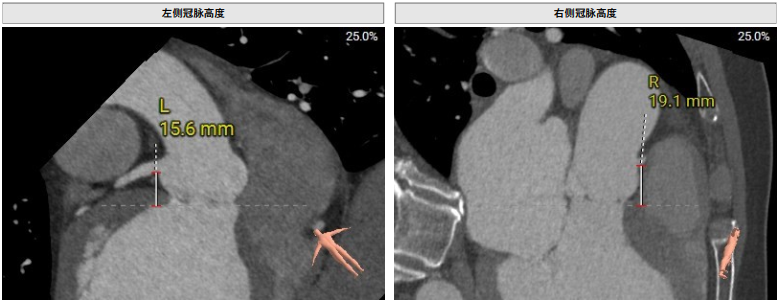

术前评估

术前影像评估提示,患者主动脉为TYPE0型二叶瓣,瓣叶增厚,边界显示不清,疑似瓣叶脱垂,少量钙化。主动脉瓣环直径31.5mm,左心室流出道直径35.3mm,STJ直径32.3mm,升主动脉直径37.3mm,冠脉开口高度充足(左冠15.6mm,右冠19.1 mm),左室与主动脉夹角158°。

该患者心脏结构对于手术存在一定挑战,主要在于患者为主动脉TYPE0型二叶瓣,左右冠同窦,瓣窦部扩张,窦部最大径线42.7mm,最终手术团队根据患者解剖结构,将两枚夹持件放入同一窦内,第三枚夹持件放置在无窦内。此外,患者同种异体原位肝移植术后2年,长期服用抗排斥药物,行传统体外循环下的心脏手术风险较高。